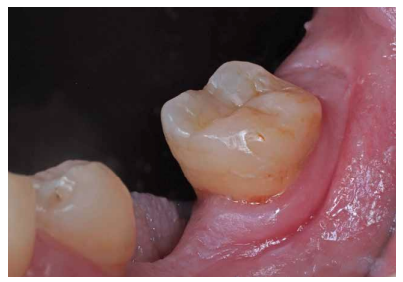

La paciente no presentaba antecedentes médicos de interés. En la exploración clínica (Figura 1) se observó que el 3.7 presentaba una lesión cariosa extensa, correspondiendo a un valor ICDAS 6, y una restauración oclusal previa de composite. En la exploración radiográfica (Figura 2) no se apreciaba banda de dentina entre la lesión cariosa y la cámara pulpar. Por tanto, según la clasificación clínico-radiográfica del International Caries Classification and Management System (ICCMS®) 4 se considera una lesión de caries severa. Presentaba un ligero ensanchamiento del espacio del ligamento periodontal en la raíz mesial y lesión apical. Se realizaron las pruebas de diagnóstico pulpar y periapical pertinentes (Tabla 1). El diagnóstico pulpar fue pulpitis irreversible sintomática y el diagnóstico periapical fue periodontitis apical sintomática.